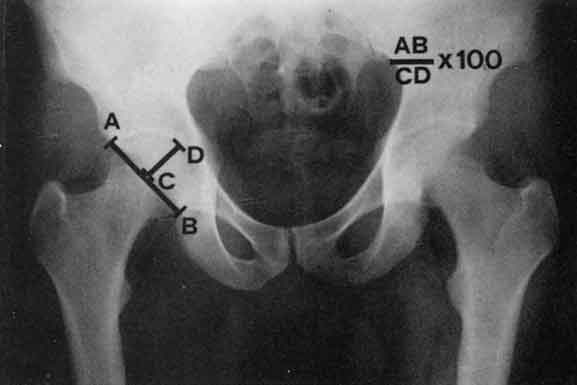

Indice acetabolare di Heyman-Herndon

Fornisce dati relativi alla profondità acetabolare ed alla sfuggenza del tetto. Viene ottenuto ponendo in rapporto due linee: la prima (AB) che unisce i punti estremi, superiore ed inferiore, del profilo acetabolare e la seconda (CD) che parte dal punto più profondo del colile e raggiunge la prima, formando con questa un angolo retto.Le due misure, espresse in millimetri, vengono messe in rapporto tra loro ed il risultato moltipllcato per cento. Nel soggetto normale il valore finale sarà del 100%.